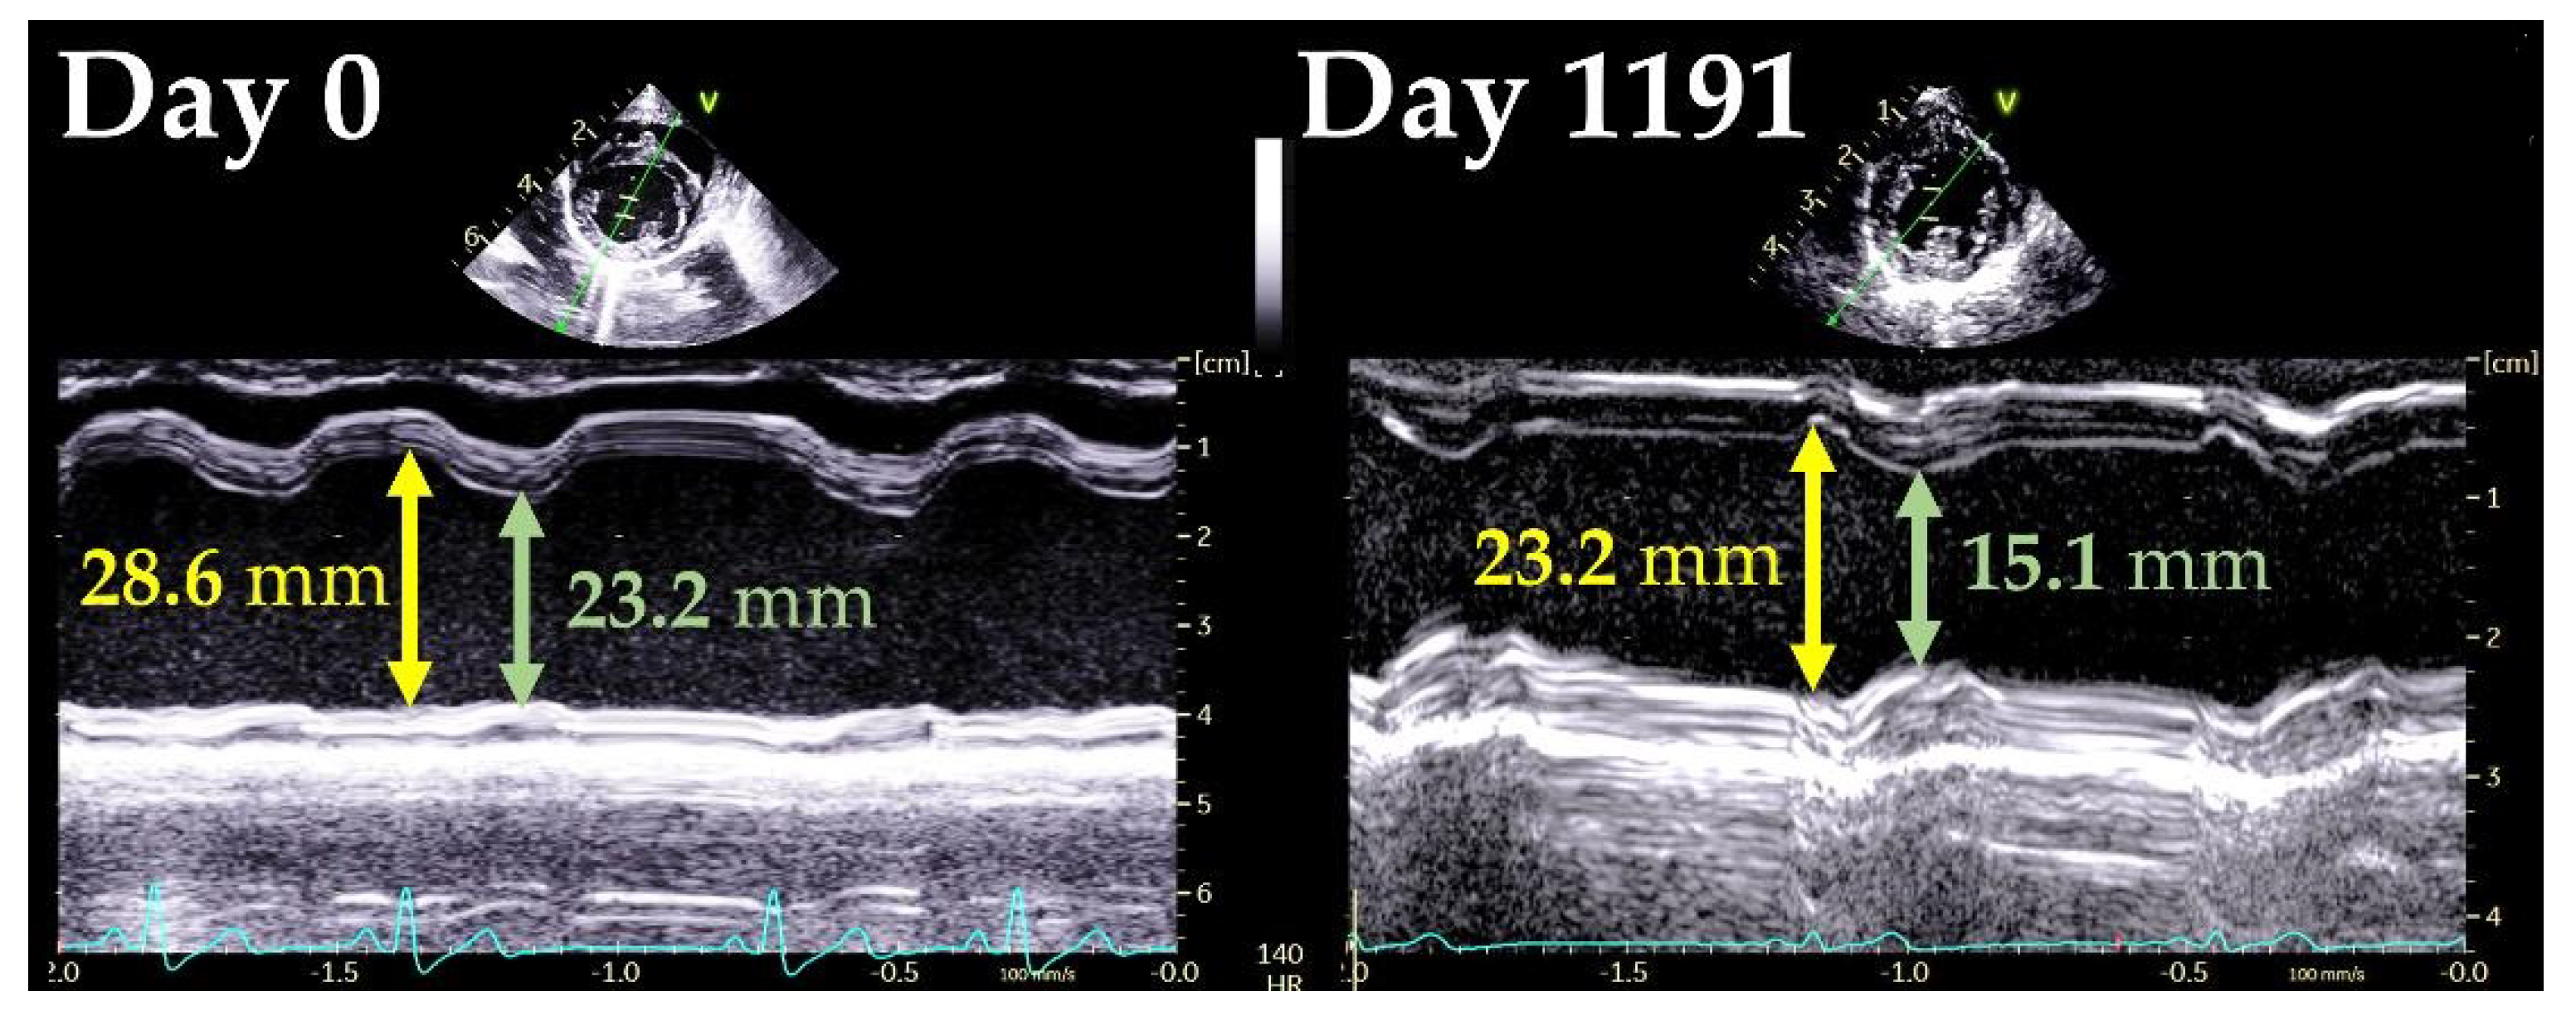

| LVIDd (mm) | 28.6 | 23.2 |

| LVIDs (mm) | 23.2 | 15.1 |